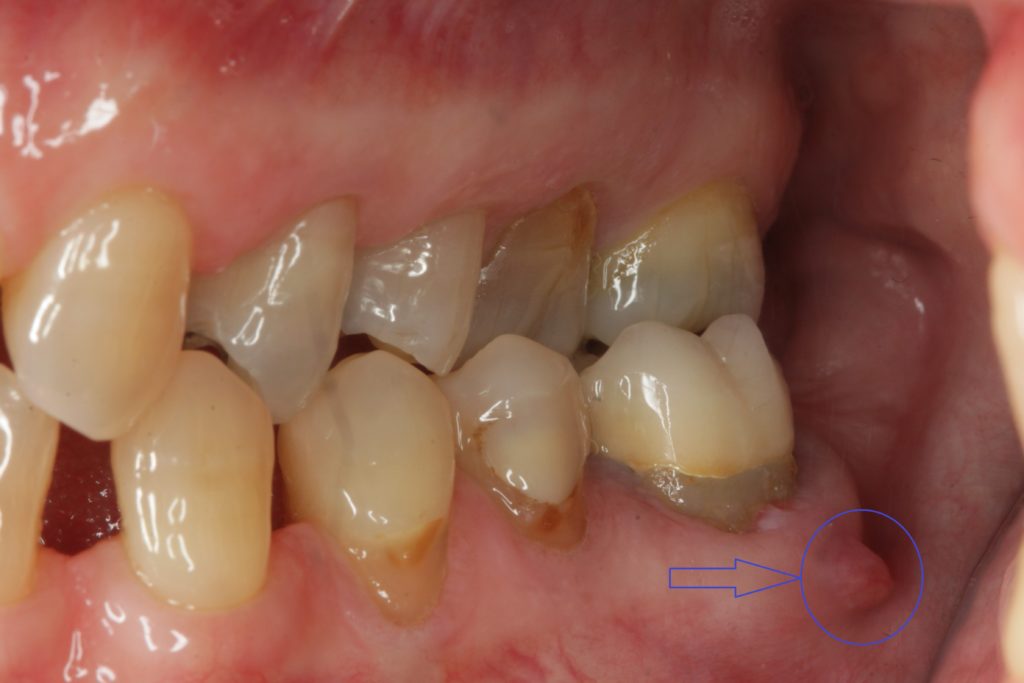

Dal punto di vista clinico, la fistola gengivale appare come una piccola protuberanza o rigonfiamento sulla gengiva, spesso di colore rossastro o biancastro. Può presentarsi come un piccolo forellino o canale visibile sulla superficie gengivale, attraverso il quale può fuoriuscire pus o altro liquido purulento in maniera spontanea o premendo il tessuto circostante.

La funzione principale del canale fistoloso è proprio quella di permettere il drenaggio del pus, alleviando temporaneamente la pressione e il dolore causati dall’accumulo di materiale infetto. Tuttavia, questa “soluzione” naturale del corpo non risolve la causa principale del problema, che richiede sempre un trattamento odontoiatrico appropriato.